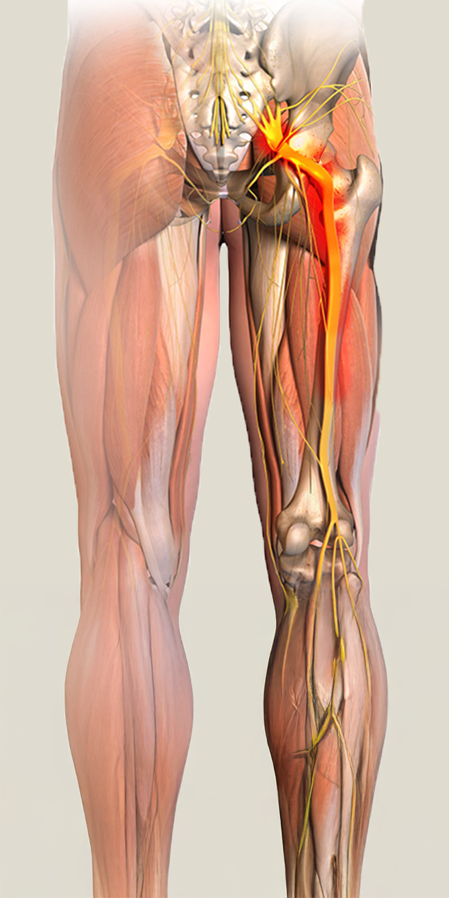

Iskiashermo on kehon pisin hermo.

Se alkaa alaselästä (L4–S1), kulkee lantion ja pakaran kautta ja jatkuu alaraajaan.

Iskiashermo voi ärsyyntyä kahdessa eri kohdassa:

Iskias syntyy, kun hermojuuri ärsyyntyy alaselän alueella (yleensä L4–S1).

Pakaran syvät lihakset, erityisesti m. piriformis, voivat painaa iskiashermoa lantion alueella.